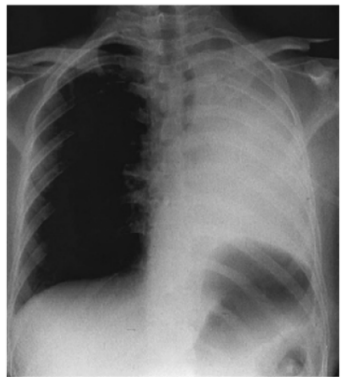

Observe a imagem a seguir.

Trata-se de uma imagem radiológica de um paciente de meia idade que apresentou início recente de dispneia intensa e hemoptise volumosa. No exame físico realizado à admissão na UTI, o fisioterapeuta observou, na avaliação ectoscópica, assimetria na movimentação torácica durante inspeção dinâmica. Ao auscultá-lo, identificou ausência total dos sons pulmonares em todo o hemitórax esquerdo. A radiografia de tórax desse caso evidencia